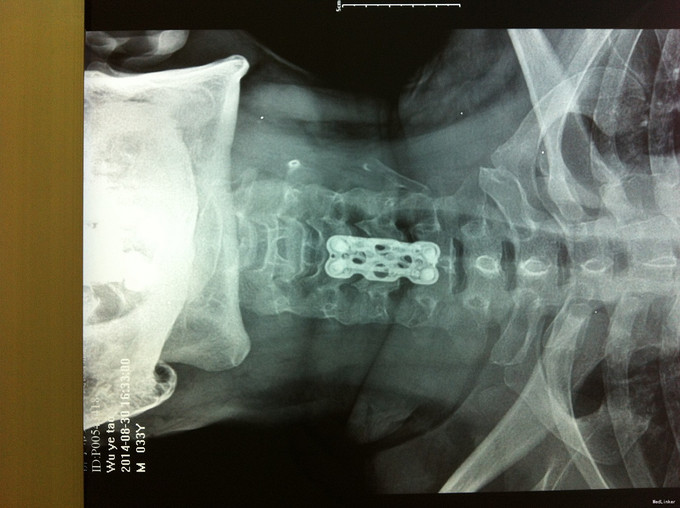

诊断:脊髓型颈椎病 处理: 1、完善相关辅助检查,明确诊断,有无手术指证; 2、全麻下行颈椎前路减压,颈椎间盘突出并骨赘形成,行颈6椎体次全切,减压较充分。

随访 1、应常规术后1个月、3个月、半年随访; 2、术后1个月,双下肢肌张力减低,行走不稳较前改善,继续服用营养神经药物。 讨论:1、颈椎病颈椎手术前路减压,两个节段椎间融合内固定术还是椎体次全切术?